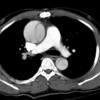

Ao Diss 1a

Date: 01/21/2006

Views: 4075